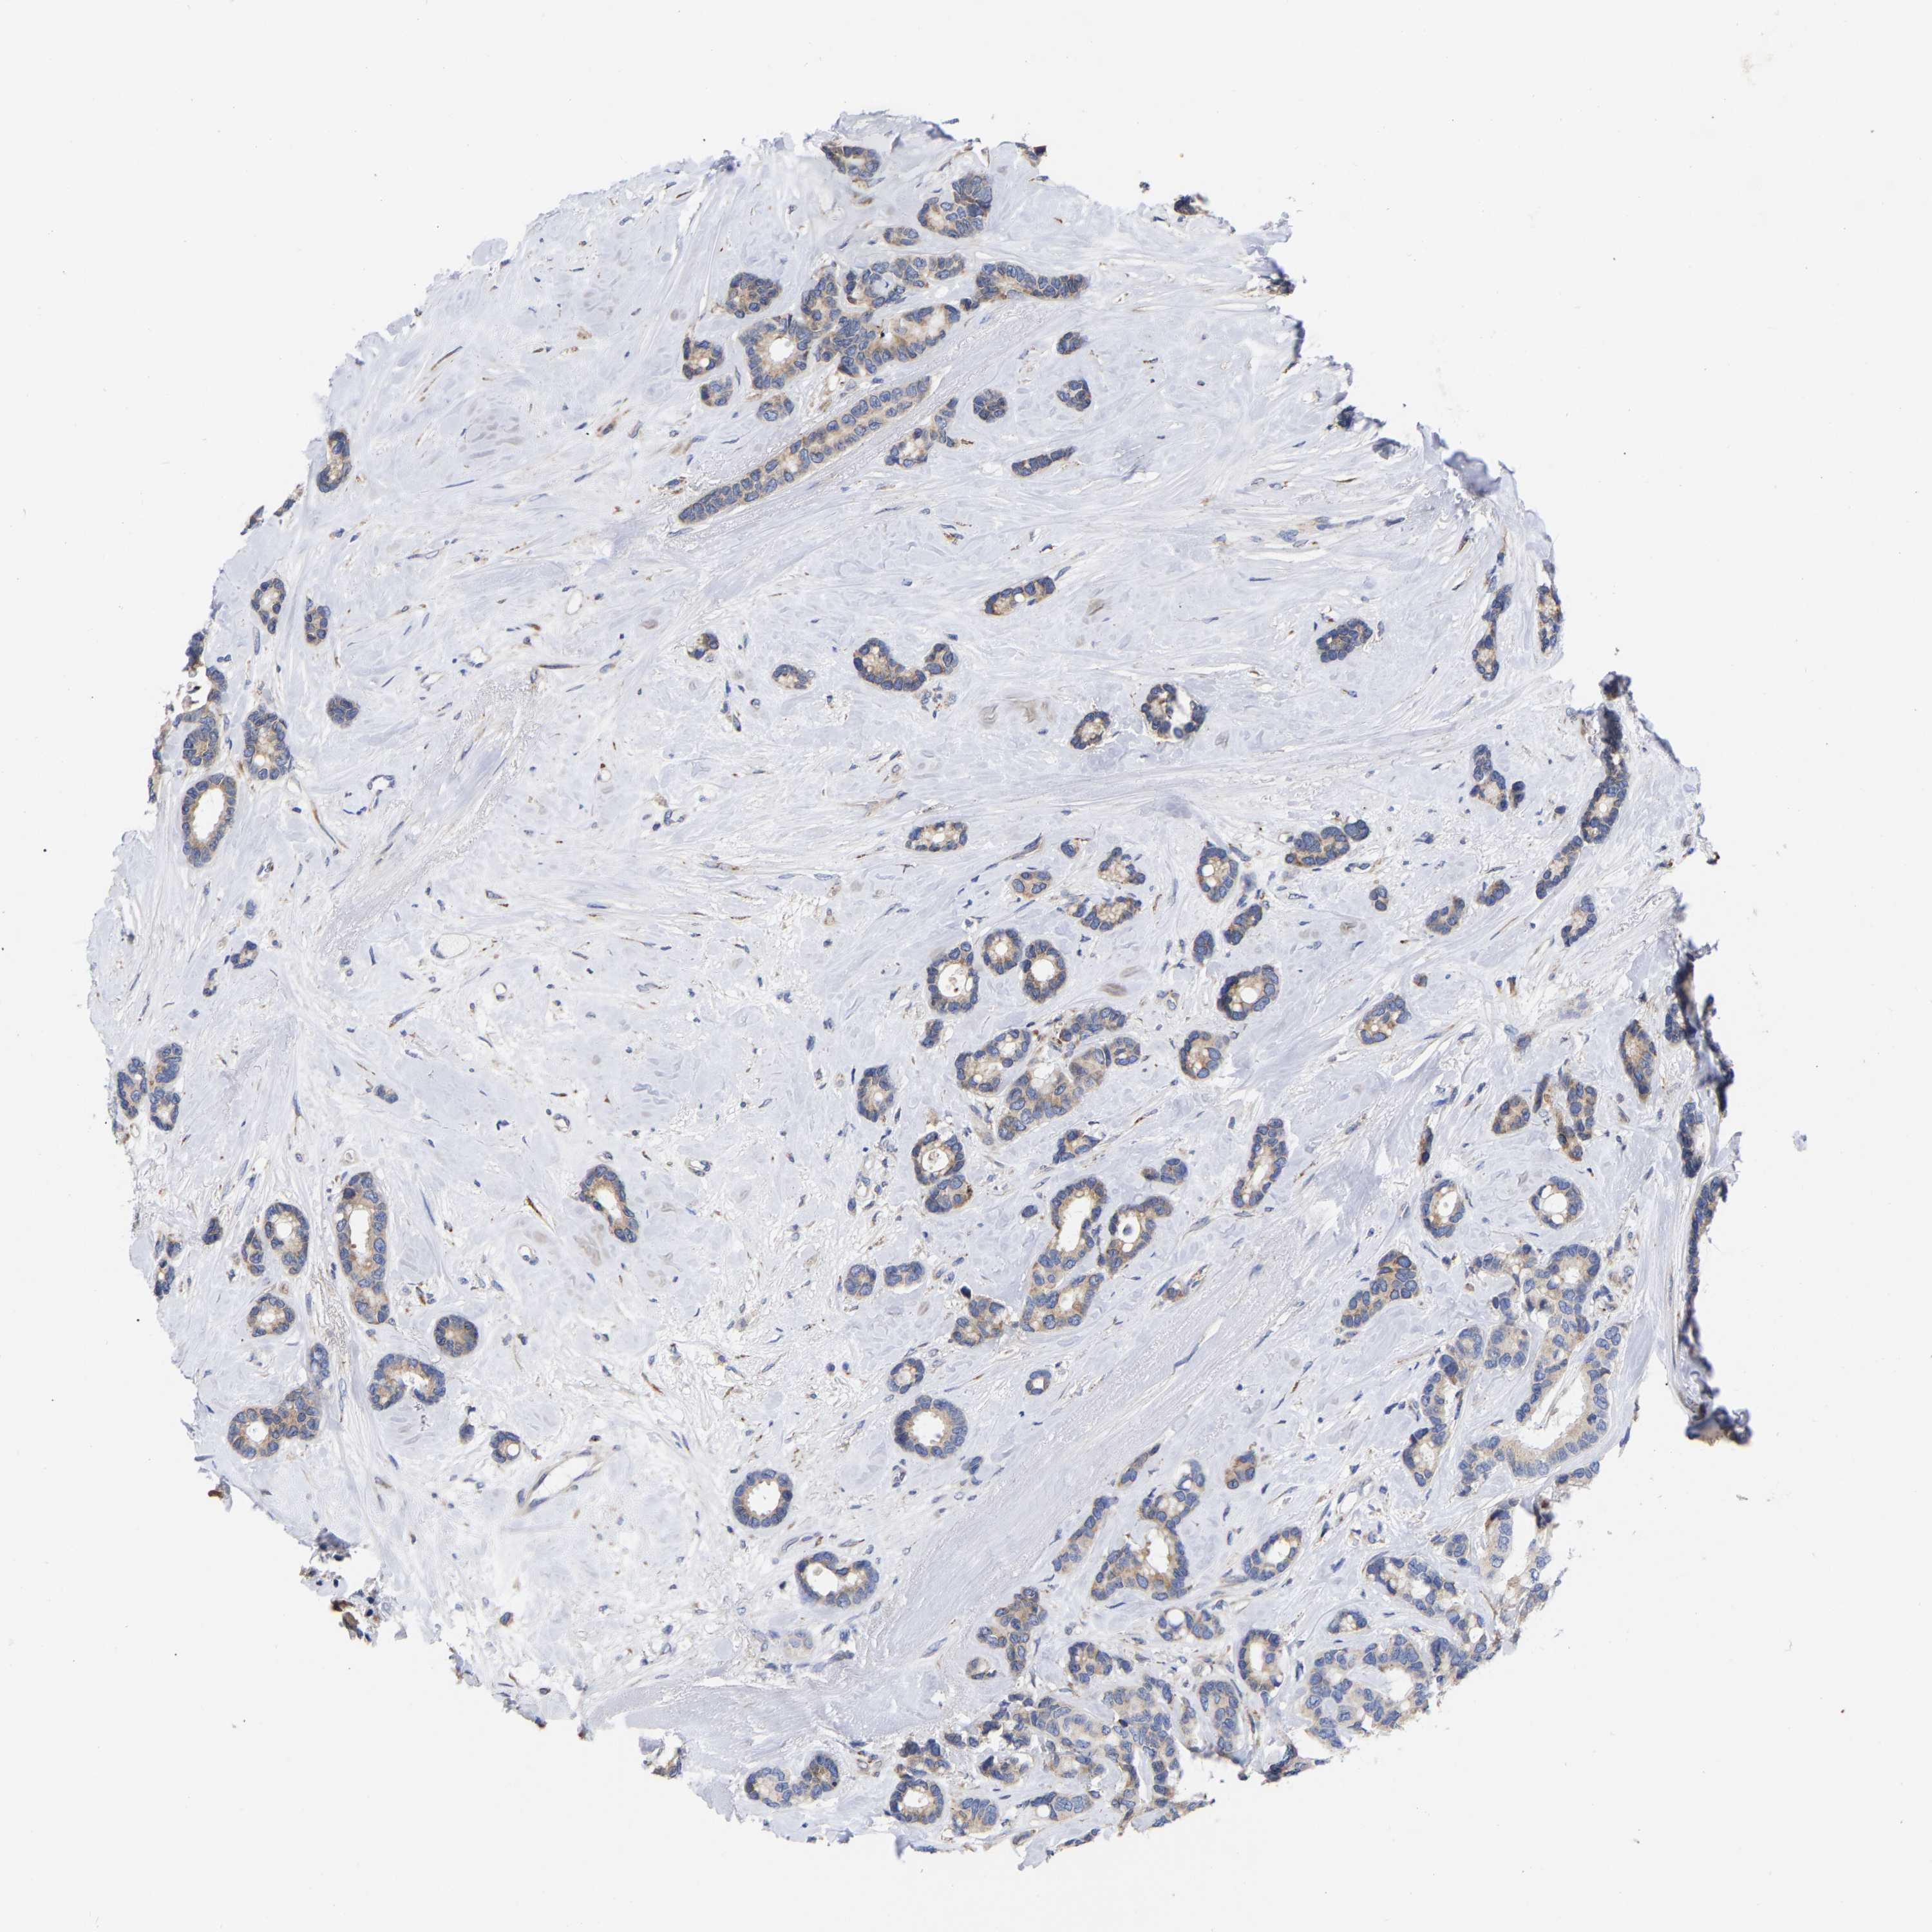

CANCER BREAST CANCER Show tissue menu

BRCA TCGA BRCA VALIDATION PROTEIN EXPRESSION